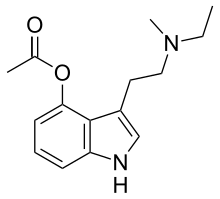

| 4-AcO-DMT | artificial | 4-OCOCH3 | CH3 | CH3 | 4-acetoxy-N,N-dimethyltryptamine | 92292-84-7 |